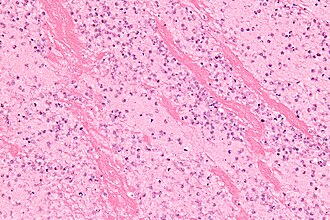

Thrombus with laminations. H&E stain. (WC/Nephron) | |

| LM | layers consisting of platelets and fibrin - classically alternating with layers of RBCs (known as lines of Zahn) |

- Layers consisting of platelets and fibrin.

- Classically alternating with layers of RBCs - known as Lines of Zahn.[2]

- Multiple laminations (layers), in general, suggest that clot was formed in a dynamic environment, i.e. in the context of blood flow.

The sections show layers of red blood cells alternating with fibrin and white blood cells (Lines of Zahn).